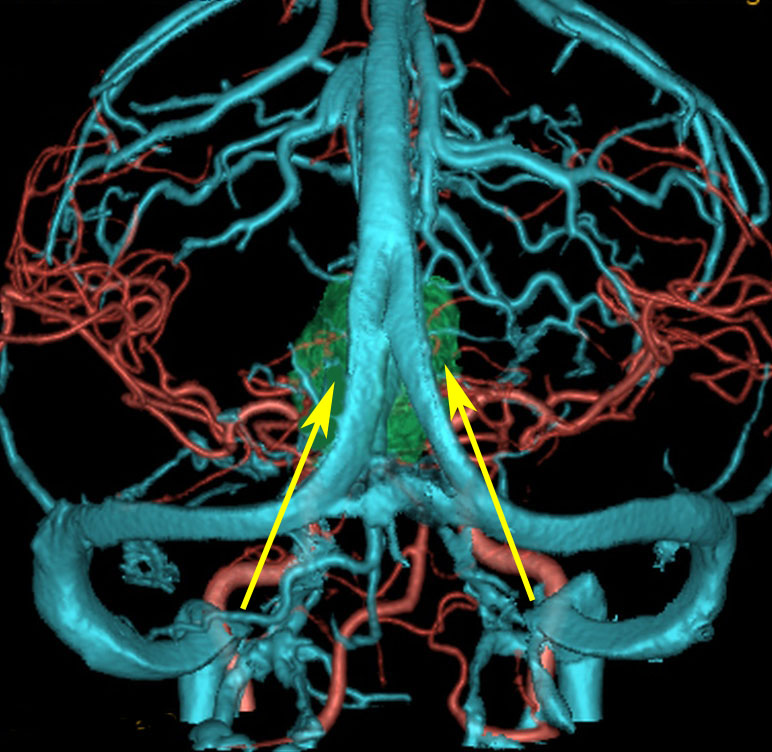

松果体腫瘍へのOTAのルートです。occipital transtentorial apporachというのは黄色の矢印に沿ってガレン大静脈の下に入る方法であり,そこから松果体部を通って第3脳室内へ直線的な視野が展開します。

一方,赤の矢印に沿ったルートは parieto-occipital transtentorial approachです。このルートでは内大脳静脈 internal cerebral veins を見ることがかなり難しいです。更に,第3脳室に入るためには脳梁膨大部 spleniumを切断する必用があります。ただし,小脳上部や第4脳室を見るときにはparietal寄りのルートを使います。

この2つのルートを混同している脳外科の先生はとても多いと思います。OTAとは,外後頭隆起を削除して,後頭極(後頭葉)を牽引して,テントの全長を切開しなければ遂行できない到達法であることを認識して下さい。

上矢状洞が左に屈曲していれば右後頭部から入ります(中断の図)。右側から入れば,右の外側(右視床や右脳迂回槽)が正中(矢状洞)側から見やすくなります。対して左側を見るときには後頭葉面からの視野になります。

逆に,矢状洞が右に寄ってるのであれば,左後頭開頭をして,左の後頭極を牽引して,大脳半球間裂の右側から入った方が,松果体部などの中心構造はよく見えます。右利きの術者は左後頭開頭の方が右手を第3脳室上壁に入れやすいです。